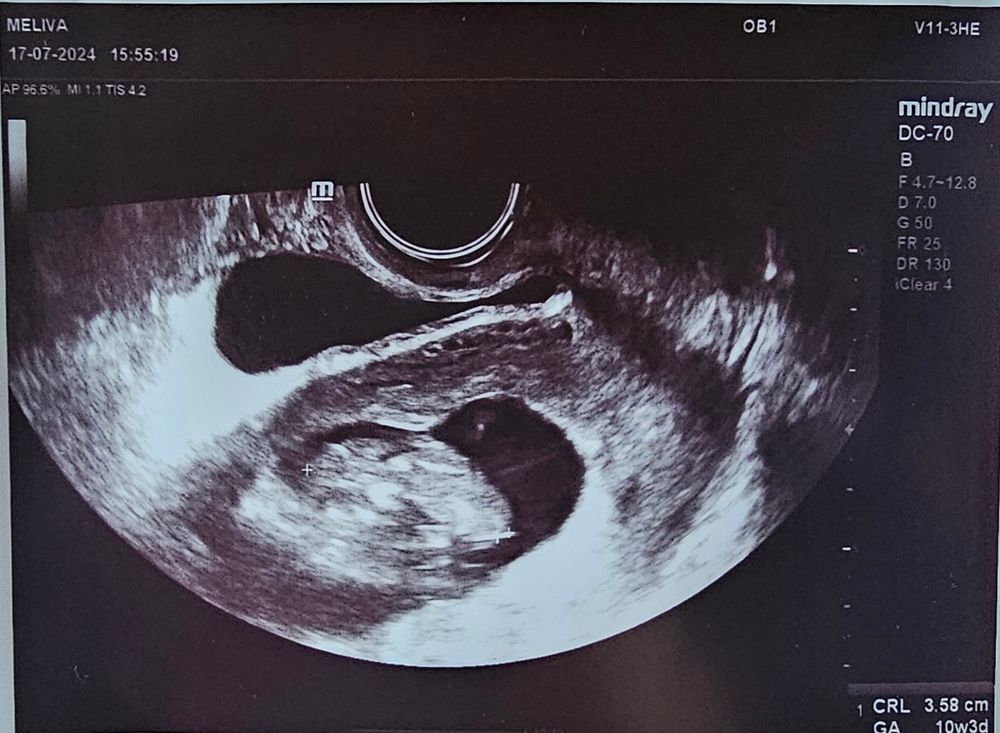

10+3 УЗИ 🥹💕🌸

Вчера была на УЗИ, поставили на учет, заказали анализы, поставили время первого скрининга (29.07).. второй раз увидела эту крошку 🥹

Поплавала, пошевелилась, помахала ручками🥹 После 2 замерших на раннем сроке, видеть, как этот маленький человечек плавает, шевелет ручками и ножками.. очень необычное и трогательное чувство. Внутри сразу трепет какой-то появился и, конечно, немного страха, что внутри меня такая малюточка. 💕💞 В каком-то смысле даже не верится, как сон какой-то.. очень люблю эту кроху и жду нашей встречи🌸💕